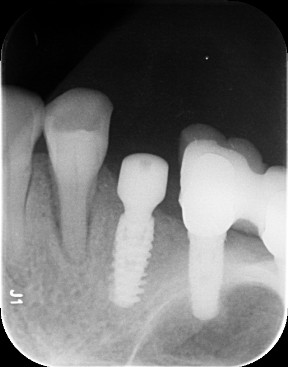

种植二期,拍片检查

旋出愈合帽,局部冲洗吹干。在就位导板的引导下旋入种植基台,拍片确认基台到位。全瓷冠试戴,冠边缘密合性良好,邻接良好。

术中戴牙拍片